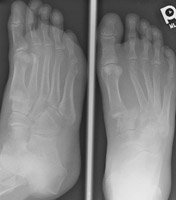

Lisfranc Fracture-Dislocation |

The Lisfranc fracture-dislocation is a term for the most common dislocation in the foot, consisting of dorsal dislocation of the tarsometatarsal joints. This entity is common in Charcot joints. Homolateral dislocation consists of lateral dislocation of metatarsals one through five or two through five. Divergent dislocation consists of lateral dislocation of metatarsals two through five and medial dislocation of metatarsal one. The injury is due to severe plantarflexion of the foot with folding of the midfoot upon the forefoot. This can be seen in parachute jumpers.